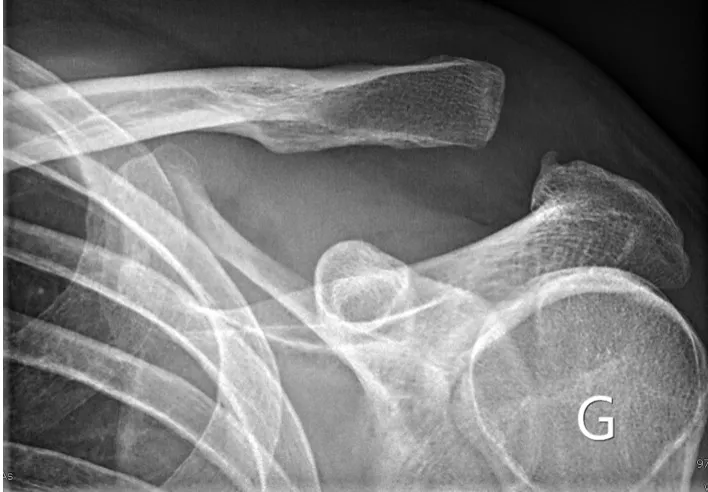

Il existe une déformation de la face supérieure de l'épaule avec un aspect saillant de l'extremité latérale de la clavicule sous la peau. L'importance de la déformation est variable en fonction de la gravité des lésions.

Dans un premier temps des radiographies permettent d'avoir une orientation diagnostique en corrélation avec l'examen clinique du chirurgien. Des clichés comparatifs (des deux épaules) permettent d'affiner le diagnostic. Un scanner avec des reconstructions tridimensionnelles peut être utile dans certains cas.